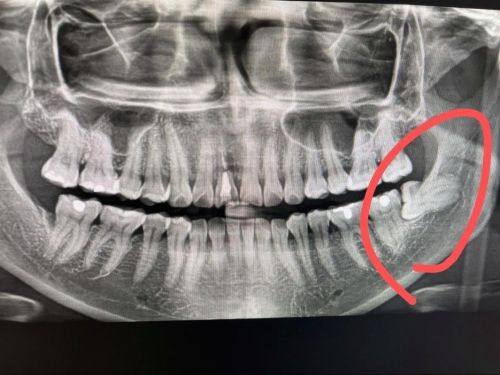

微创拔牙:擅长埋伏多生牙、阻生智齿的微创拔除,采用微创技术减少手术创伤,患者术后修复快,不适感低,医生操作专精,能有效降低拔牙风险。

贺吉凯:主事医师,从事牙科诊疗工作10多年,毕业于潍坊医学校,接受过规范化及种植专科培训,熟悉多套国内外精良种植系统,擅长埋伏多生牙、阻生智齿的微创拔除、即刻种植修复、骨增量手术,在复杂牙拔除及种植牙领域拥有丰富的理论基础和临床经验。